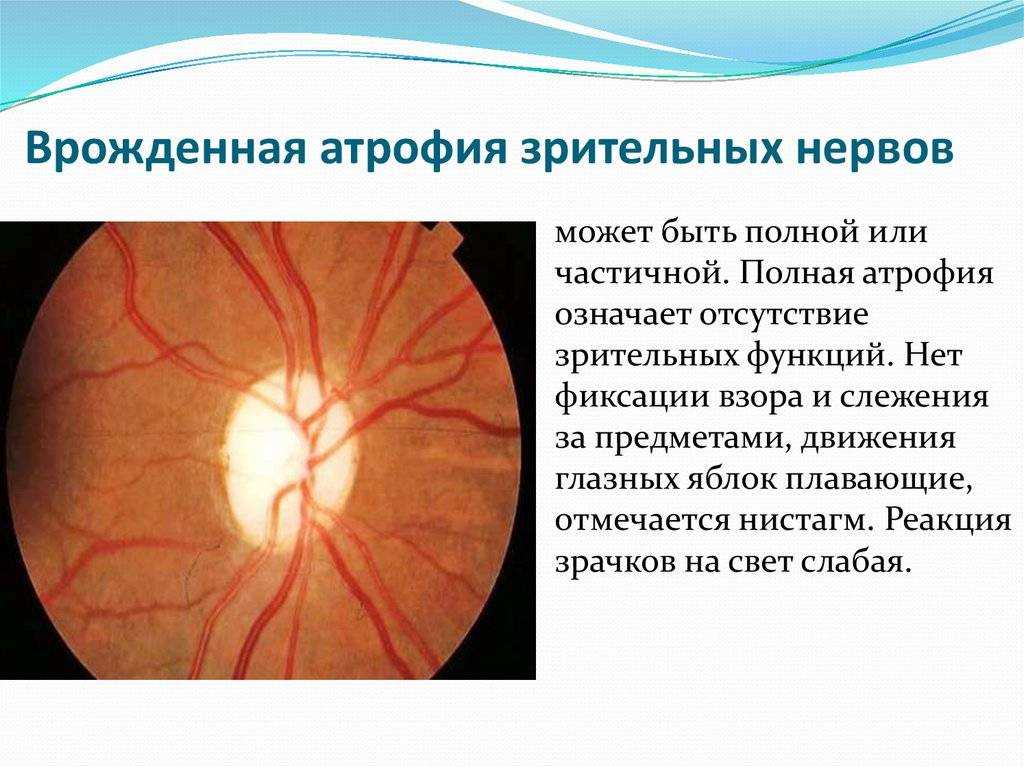

Атрофия зрительного нерва Лебера: Симптомы и лечение